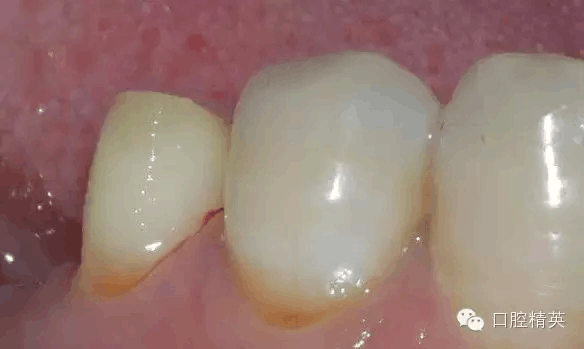

排齦后,制備肩臺(tái)